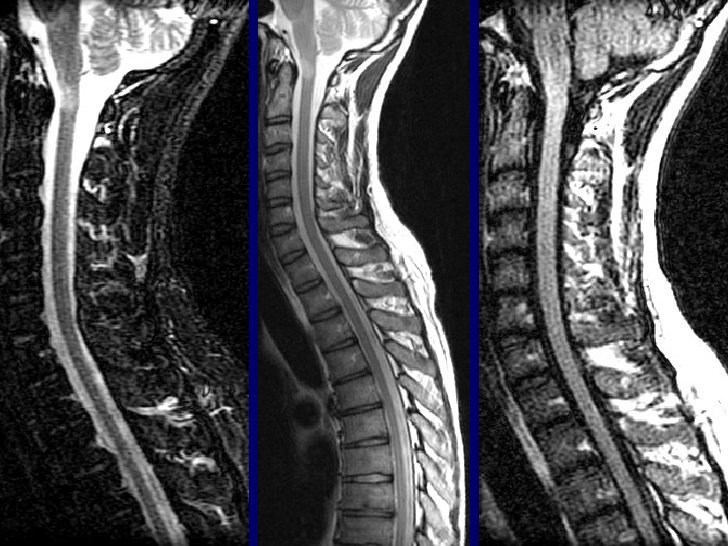

3.2. Chụp cộng hưởng từ (MRI)

Chụp cộng hưởng từ cho phép xác định được vị trí, hình thái thoát vị, số tầng thoát vị. Đây được coi là phương pháp chẩn đoán hình ảnh hiện đại và chính xác nhất trong các phương pháp chẩn đoán thoát vị đĩa đệm cột sống thắt lưng.

Bên cạnh đó, cộng hưởng từ còn giúp chẩn đoán tốt các tổn thương ở thân đốt sống, tủy sống, đĩa đệm và tổ chức phần mềm quanh cột sống. Hình ảnh cột sống thu được từ MRI rõ nét và chi tiết.